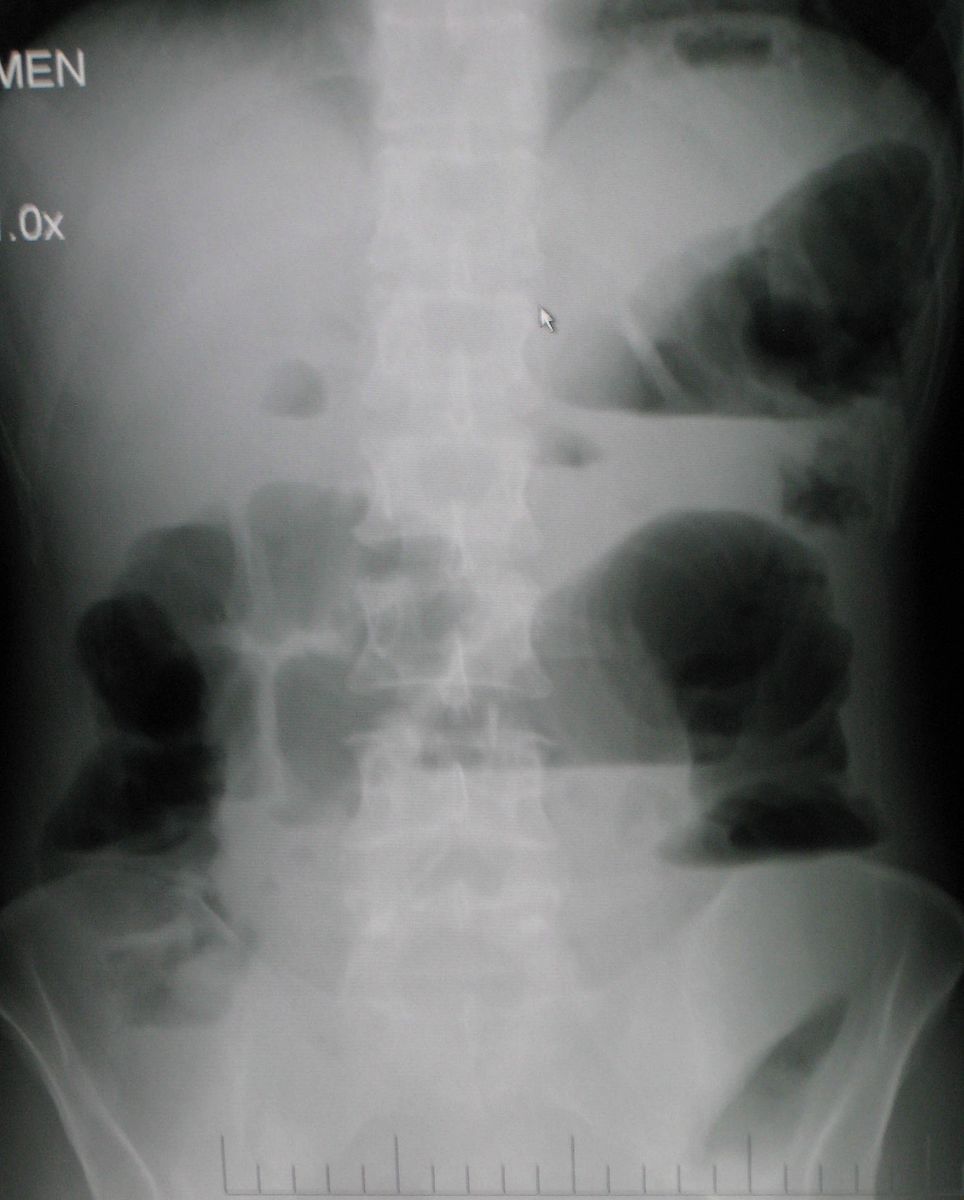

Example 2

Diagnosis

Small Bowel Obstruction